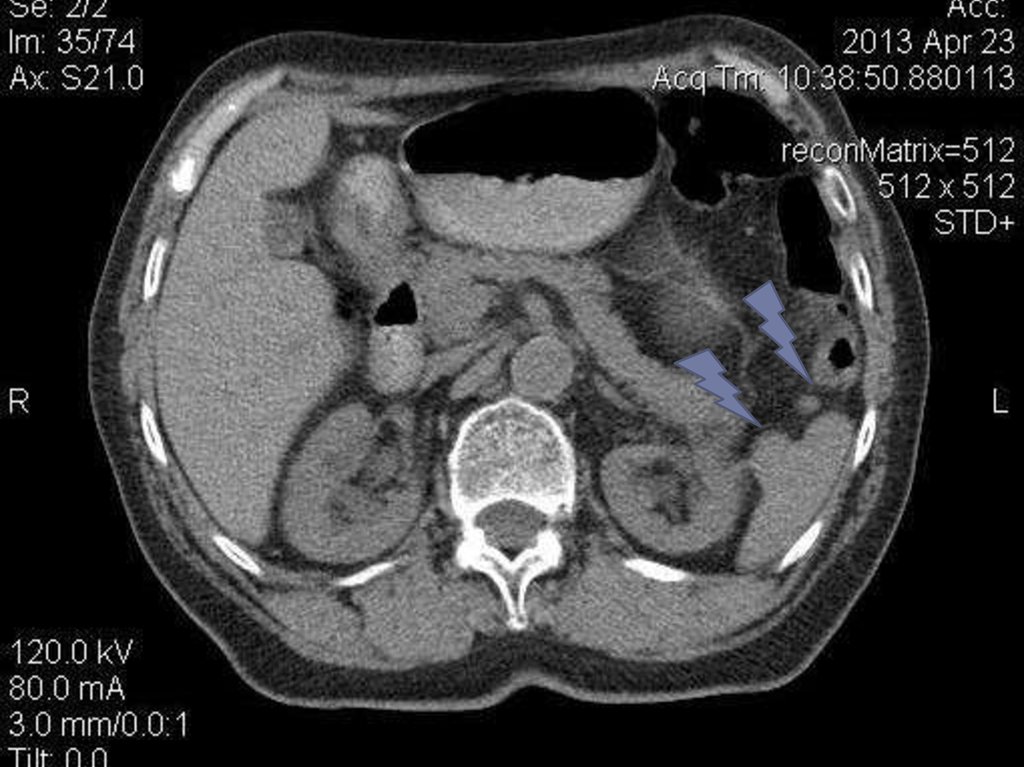

7. Lien(splen)-в левом подреберье на уровне IX-XI ребер по средней подмышечной линии.